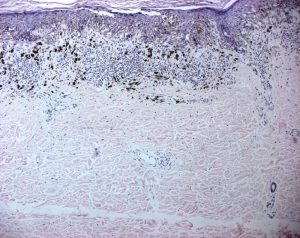

Esame istologico

Entrambe le lesioni sono state sottoposte ad asportazione chirurgica.

- Lesione addominale: melanoma a diffusione superficiale a cellule fusate, con discreta risalita intraepidermica (Melanoma Livello II, 0,7 mm secondo Breslow).

- Lesione del braccio sinistro: melanoma in fase verticale di invasione (Melanoma Livello III, 2,2 mm secondo Breslow).